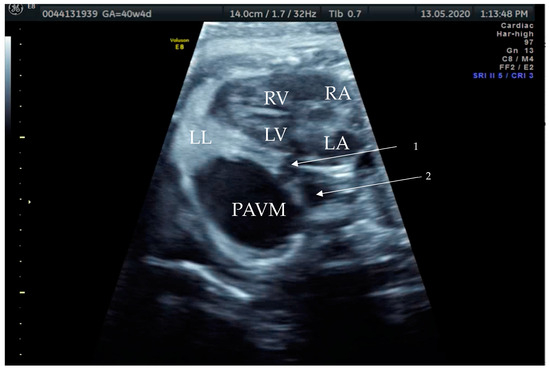

Figure 1. Prenatal B-Mode transabdominal ultrasound picture with cystic structure on the level of four chamber view with a clear linkage of the structure to the left atrium. RV—right ventricle, LV—left ventricle, RA—right atrium, LA—left atrium, LL—left lung, PAVM—pulmonary arteriovenous malformation, arrow—showing the connecting vessel to the left atrium and the PAVM. Actually, this finding led to the suspicion of PAVM. We needed to prove it with color Doppler, as shown in the next picture.